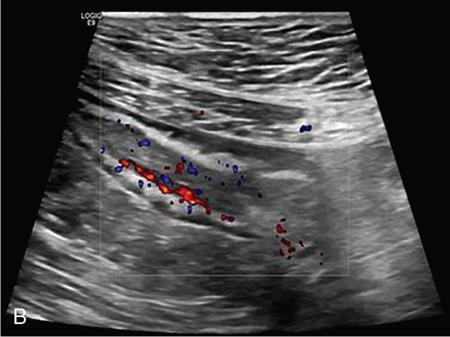

Kavita Saggar, Archana Ahluwalia, Devinder Pal Singh Dhanota, Geetika Khanna, Chander Gupta Inflammatory bowel disease (IBD) represents chronic idiopathic inflammation of the gastrointestinal [GI] tract. The common subtypes are Crohn’s disease, ulcerative colitis (UC) and indeterminate colitis (Fig. 7.11.1). Approximately 20%–25% of patients present in childhood or adolescence. Of these, nearly two-thirds of cases are caused by Crohn’s disease with an incidence of 4.56 per 1000,000 children (Fig. 7.11.2). IBD can affect any portion of the GI tract; however, children have a much higher incidence of small bowel and colonic involvement (Table 7.11.1). Currently, there is no single diagnostic test for the evaluation of IBD. Diagnosis is based on a combination of history, physical examination, serum inflammatory markers, endoscopy, histopathology and imaging. A host of imaging modalities is available for the evaluation of IBD in children. Traditionally, barium fluoroscopic studies, namely small bowel follow-through or small bowel enteroclysis (SBE) were used. However, barium studies depict only the mucosal abnormalities and do not evaluate the extraluminal extent of disease. Ultrasonography (US) is increasingly being used in the workup of patients with IBD. Small intestine contrast ultrasound (SICUS) and contrast-enhanced ultrasound (CEUS) are used for evaluation of IBD. CEUS requires intravenous administration of microbubble contrast such as Sonovue, and SICUS requires small bowel adequate luminal distension with ingestion of an iso-osmolar contrast agent such as polyethylene glycol. A recent meta-analysis of 33 studies showed that CEUS had better accuracy than US, CT and MR for the detection of inflammation and differentiation of fibrotic and inflammatory strictures. However, the extent of the disease was better evaluated by CT and MR. Currently, computed tomography enterography (CTE) and magnetic resonance enterography (MRE) have emerged as the most effective tools for imaging small bowel in patients with IBD. CTE and MRE can accurately depict the spectrum of imaging findings related to severity, extent and complications of IBD and thereby help in guiding management and assess the response to treatment. MRE is an attractive imaging modality due to lack of ionizing radiation, inherent multiplanar capability and excellent soft tissue contrast resolution. In addition, dynamic/cine imaging allows assessment of peristalsis and accurate identification of the diseased segment. The major disadvantage of MRE is high cost, lower spatial and temporal resolution and long examination time. Crohn’s disease is a transmural granulomatous disease that can affect any part of the GI tract from the oral cavity to anus, often involving multiple discontinuous segments of bowel. Patients have a genetic predilection to develop an abnormal immunologic response to environmental factors including food and gut flora, leading to a chronic inflammatory response. Small bowel is the major site of involvement. Terminal ileum is the most common location which is involved in approximately one-third patients. The colon is affected in 50% patients. In 15%–20% cases, there may be isolated involvement of the colon without affecting the small bowel. The clinical importance of small bowel Crohn’s disease is the impact that a diffuse small bowel disease is expected to have on child’s growth and development. Thus, objective evaluation of small bowel is essential in differentiating from other enteropathies and in directing the management of patients with IBD. Two methods used for imaging small bowel with barium using fluoroscopy are standard small bowel follow through (SBFT) and SBE. Small bowel evaluation with barium has long been considered the most common, noninvasive, inexpensive and easily accessible radiological method, but it has been replaced by cross-sectional imaging. In the current scenario, the only indication of barium studies is when CTE or MRE cannot be done because of nonavailability or are not feasible. Ultrasound is being increasingly used to assess the activity of Crohn’s disease, especially in paediatric patients. Greyscale ultrasound allows morphologic assessment of bowel wall and mesentery. Normal small bowel loops are easily compressible with the transducer and the wall thickness is <2 mm. The bowel loops show regular peristalsis and are mobile. Colour Doppler shows minimal intramural or perienteric vascularity. The salient sonographic features of Crohn’s disease are: There is marked concentric or eccentric bowel wall thickening [>2.5–3 mm]. The mural echogenicity depends upon the degree of inflammation and fibrosis. In the acute phase, mural stratification is maintained (Fig. 7.11.3A and B). In patients with long-standing disease, a target or pseudo-kidney appearance may be seen. In long-standing burnt-out disease, there is submucosal fat deposition. The actively inflamed bowel segments show increased vascularity on Doppler ultrasound (Fig. 7.11.4A and B). CEUS with microbubbles can objectively assess the disease activity. A stricture is seen as a segment of bowel wall thickening with apposition of the luminal surfaces. There is persistent luminal narrowing with variable degree of upstream dilatation and hyperperistalsis. Doppler imaging reveals hyperemia in strictures with an active inflammatory component. Fibrotic strictures do not demonstrate increased blood flow. A major advantage of ultrasound is real-time imaging which allows the evaluation of bowel peristalsis. The diseased segments of the bowel (inflamed or fibrotic) show reduced peristalsis and often appear fixed in position. Mesenteric inflammation is commonly seen in active Crohn’s disease. Sonography reveals thickening of mesentery with heterogeneous echogenicity due to oedema. Doppler ultrasound shows increased vascularity due to engorgement of vasa recta. Fibrofatty proliferation of mesentery seen in chronic disease appears as abnormally thickened echogenic fat that displaces the bowel loops. Reactive mesenteric lymph nodes (up to 1.5 cm) can be seen in the active inflammatory phase of Crohn’s disease. These appear as hypoechoic round or oval structures with preserved fatty hilum. Sinus tracts and fistula often arise from or just proximal to a strictured segment and appear as linear areas of altered hypoechogenicity extending from serosal surface of gut. There may be tethering and/or angulation of the affected bowel segment. Abscesses are discrete well-defined fluid collections with internal debris, septation or nondependent echogenic gas. Colour Doppler reveals peripheral hyperemia with absent blood flow centrally. Ultrasound may be falsely negative if an abscess contains a large amount of air and can be mistaken for an air-filled bowel loop. Both CTE and MRE identify the transmural, extramural and mesenteric manifestations of small bowel Crohn’s disease. The imaging findings can be categorized as: Asymmetric long segment (>3 cm) bowel wall thickening is a consistent feature of Crohn’s disease. The mesenteric border is usually more severely affected. It is imperative that the bowel should be distended when assessing bowel wall thickening. Thickening may be mild (3–4 mm), moderate (5–10 mm) or severe (>10 mm) (Fig. 7.11.5A and B). This is the most consistent finding in the active inflammatory stage, defined as increased signal intensity or attenuation on contrast-enhanced scans in a noncontracted segment of bowel in comparison with adjacent small bowel segments. Hyperenhancement may be stratified into bilaminar and trilaminar patterns. In the bilaminar pattern, there is hyperenhancement of only the inner wall (often referred to as mucosal hyperenhancement), and in the trilaminar pattern, there is inner and outer wall hyperenhancement, with the submucosal oedema giving a halo effect. Hyperenhancement may also be homogeneously transmural or patchy. A potential pitfall in contrast enhancement is that normal jejunal loops enhance more than ileal loops and collapsed bowel segments can show apparent hyperenhancement (Figs. 7.11.6A,B and 7.11.7A–C). These are defined as multifocal (>3) segmental areas of involvement with normal intervening gut loops. This is an important feature that differentiates Crohn’s disease from UC when colon is predominantly involved (Figs. 7.11.5A,B and 7.11.7A–C). This is identified as an increased signal of the thickened bowel wall on T2W images. The inflamed walls also show restricted diffusion. The hyperintense signal due to intramural oedema persists on T2W fat-saturated images differentiating it from intramural fat seen in long-standing burnt-out disease (Fig. 7.11.8A and B; refer Fig. 7.11.20A–D).